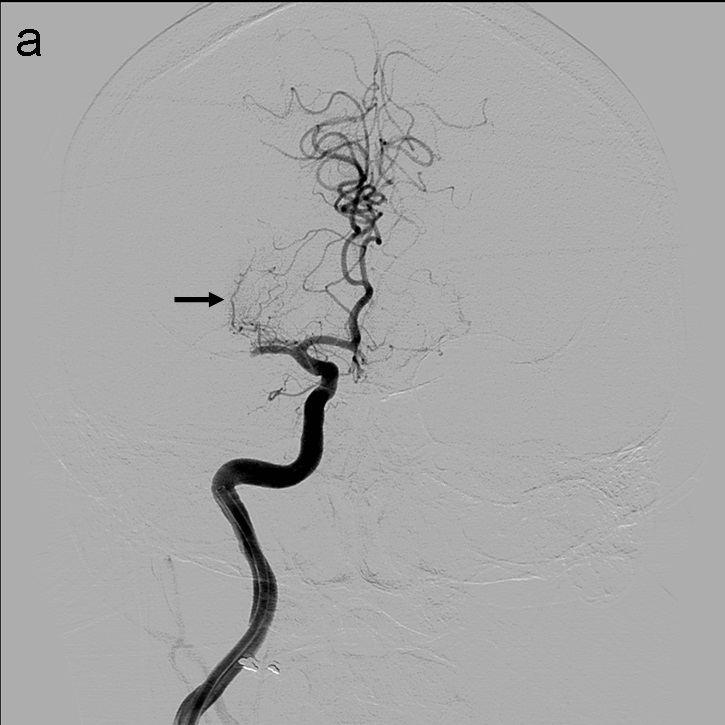

La técnica ADAPT consiste en usar el microcatéter y la microguía con el fin de facilitar la navegación del catéter de aspiración hasta aproximadamente 1-2 cm del trombo, momento en el que se retiran la microguía y el microcatéter y la llave en ‘Y’ avanzando el catéter de aspiración hasta que deja de refluír sangre por el ‘hub’. Tras esto se conecta la bomba de aspiración, se hincha el balón del FlowGate2 (imagen 2) con contraste diluido (50:50), se aspira con una jeringa de 50 cc través de éste último y se realiza el pase retirando el catéter aspiración.

Se realiza una serie a través del catéter balón que demuestra una recanalización parcial del segmento M1 proximal con apertura de arterias lenticuloestriadas y persistencia oclusión de segmento M1 distal de ACM derecha (imagen 3). Se decide cambiar de estrategia y usar la técnica SAVE con Catalyst 5, Trevo Pro 18, Asahi Chikai 0.014’’ y Catch 6 x 30 mm.